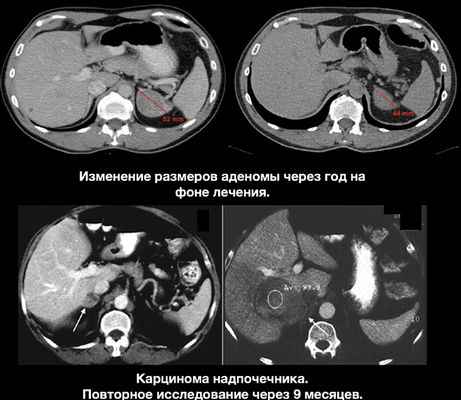

В верхнем ряду представлены изображения изменения размеров аденомы на фоне лечения. Обратите внимание, как производится измерение данной функционирующей аденомы.

- Следовательно характеризуем данное образование, как

- Стабильное в размерах в течение года и более образование.

- NB! образование должно быть измерено одним и тем же специалистом.

- Сравнение по описанию само собой не допускается!

- Рекомендуем биохимические исследование и консультацию эндокринолога.

В нижнем ряду представлены изображения пациента с верифицированной карциномой надпочечника. Данному пациенту был назначен КТ контроль через год, но не были рекомендованы консультация эндокринолога и биохимические исследования. При КТ контроле через 9 месяцев образование существенно увеличилось в размерах.